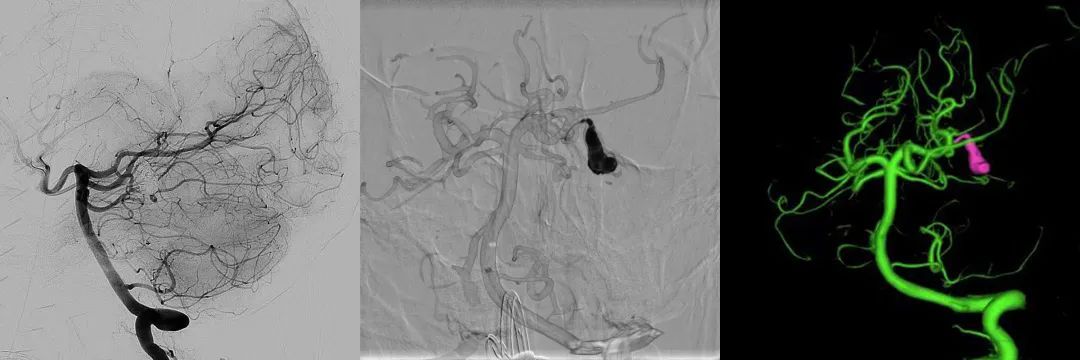

闭塞夹层动脉瘤

麻醉、微导管超选、唤醒评估、精准功能抑制、再次评估神经功能、闭塞夹层动脉瘤、滑轨CT复查——整台手术一气呵成。麻醉苏醒后,躺在手术台上的小马清晰地说出:“你们让我读‘草原’两个字……”,此时的大家都露出欣慰的笑容,经过近2小时的手术,成功为女孩拆除了脑内的“炸弹”。

多学科专家首先进行了术中唤醒后的闭塞实验,利用微导管精准注射药物抑制这根直径1毫米病变血管的功能,并以此评估手术的安全性,在准确探测出大脑内部“禁区”后,用一根直径约半毫米的微导管伸入仅1毫米的载瘤血管内,并将一枚“弹簧圈”小心送达病灶腔内,确认弹簧圈形态良好,继续用数枚弹簧圈逐步填满血管,直至“炸弹”被完全隔绝。